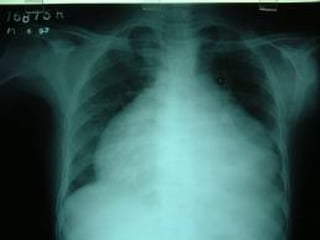

EKGEKG

Chest radiographChest radiograph

EchocardiographyEchocardiography

Radiological FindingsRadiological Findings

Normal <200mlNormal <200ml

Cardiomegaly >200mlCardiomegaly >200ml

+/- pleural fluid+/- pleural fluid

+/- pulmonary / mediastinal+/- pulmonary / mediastinal

- occasionally – small pulmonary infiltration or pleural- occasionally – small pulmonary infiltration or pleural

effusion (viral infection)effusion (viral infection)

- bacterial – in conjunction with pneumonia- bacterial – in conjunction with pneumonia